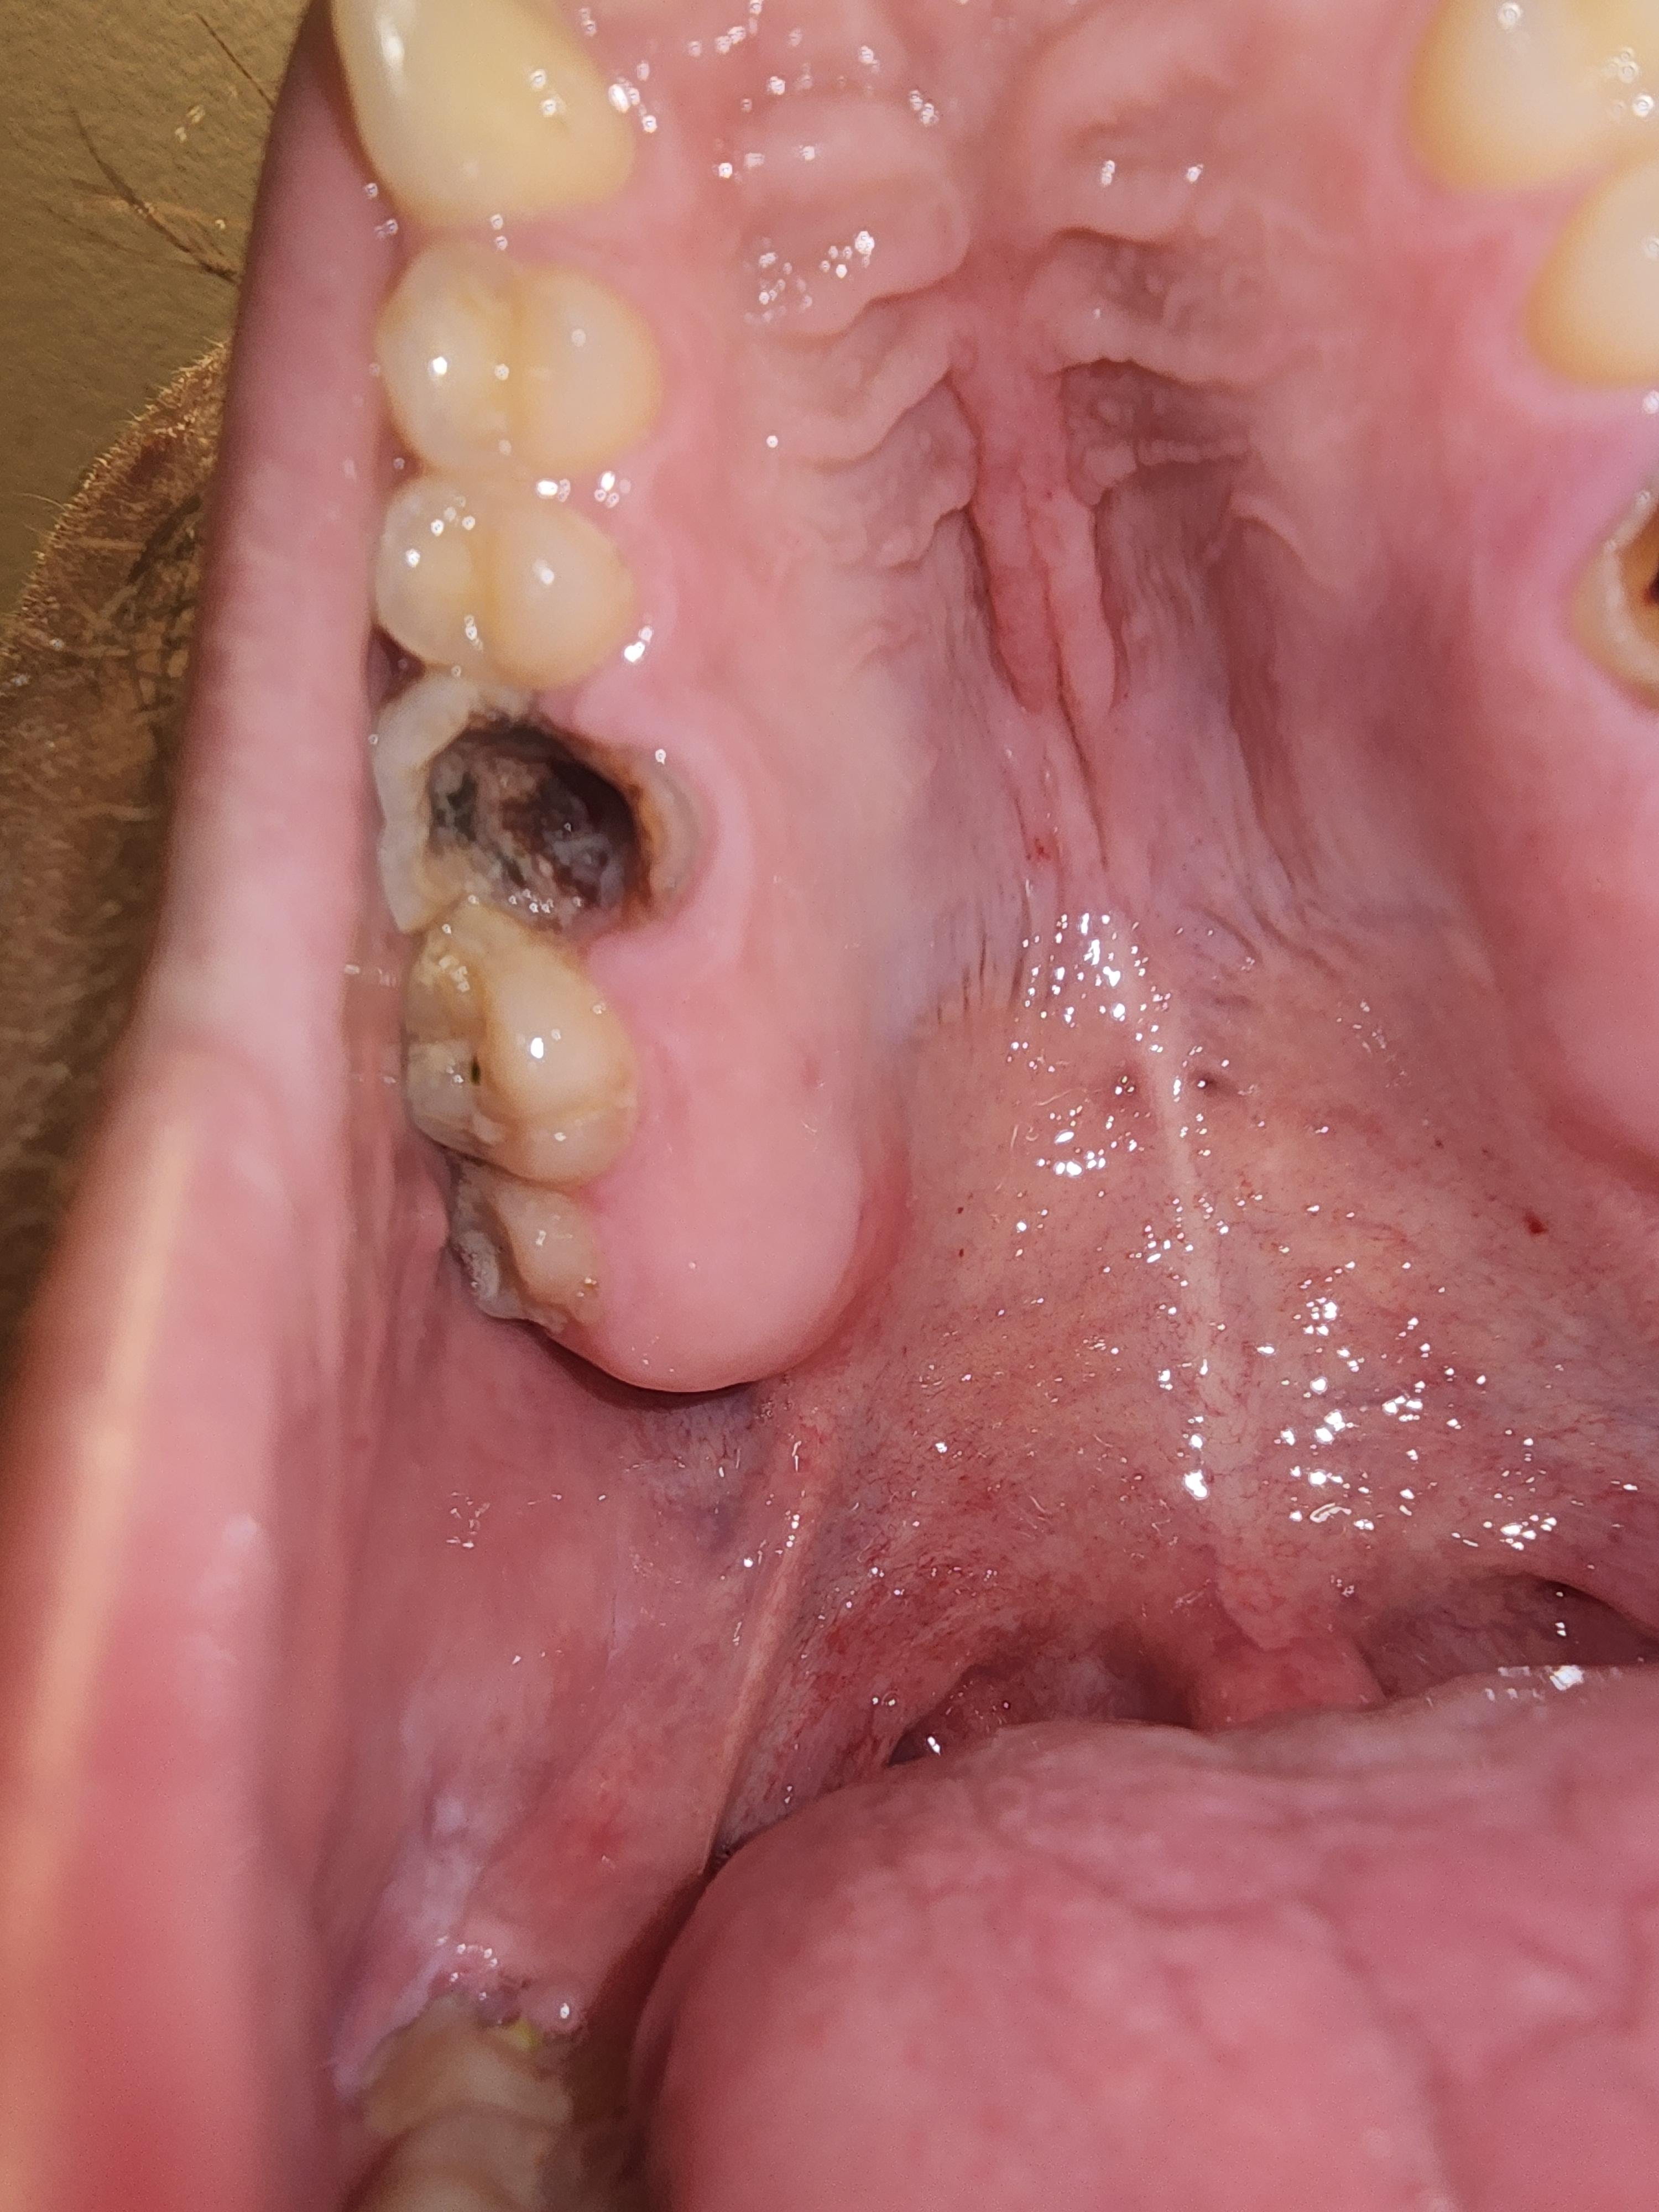

| Affected Teeth | The image primarily shows the upper right posterior molar area. It appears to involve two teeth: the First Molar and the Second Molar (possibly the second premolar and first molar depending on the perspective, but the size suggests molars). |

| First Molar (most posterior visible tooth with a dark area) | This tooth has a very large, deep carious lesion (decay) that has destroyed a significant portion of the crown, likely reaching the pulp chamber and causing pulp necrosis. The dark area could be residual decay, filling material, or the exposed root canal system. This tooth is the likely primary source of infection. |

| Second Molar (tooth in front of the decayed one) | This tooth also appears compromised, possibly with decay or a failed/old restoration. Its proximity means it may be affected by the same pathology or require concurrent treatment. |

| Swelling/Bulge | A significant, localized swelling or fistula (pimple-like bump) is visible on the gum tissue (palatal side, near the roots of the first molar). This strongly indicates a periapical abscess—a pocket of pus/infection at the root tip—that is draining, or attempting to drain, through the gum tissue. |

| Client Symptom | Bleeding from the area. This can occur due to deep decay, gum inflammation (gingivitis/periodontitis), or irritation from the swollen tissue/fistula. |

Based on the image and your description, the case involves a severely decayed upper molar with a confirmed periapical abscess (indicated by the palatal swelling/bulge) that is likely in close proximity to the Maxillary Sinus floor.